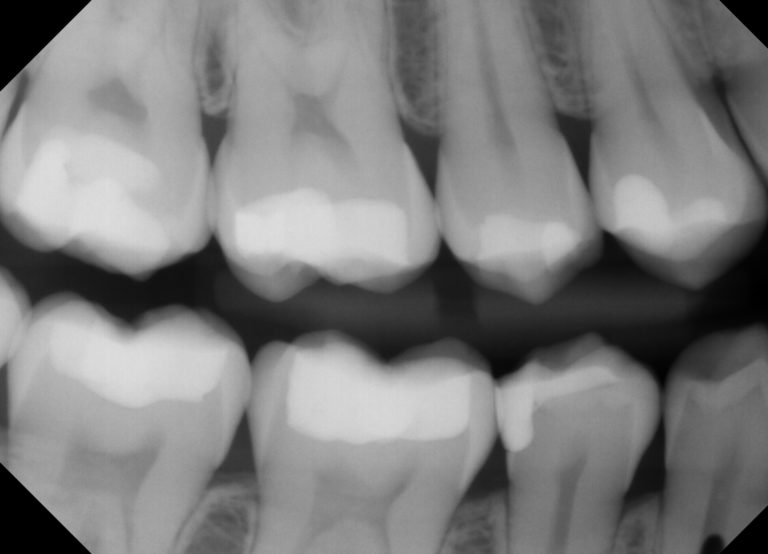

However, fillings also are the cause of fear and anxiety for many people Do cavity fillings hurt? In this post, you'll learn how to tell if you have a cavity, what the pain level is during the filling process, and more.

Do fillings hurt? Get all your questions answered about dental fillings, including pain management and aftercare tips Many people fear pain and discomfort if they need to get a cavity filled However, modern dental techniques make the process mostly painless and comfortable

Getting a Cavity Filled Hurt? Pain in Tooth After Filling?. This is a result of using highly effective numbing. Let's learn more about cavity filling pain, what to expect during the procedure, and how to manage any discomfort that follows.